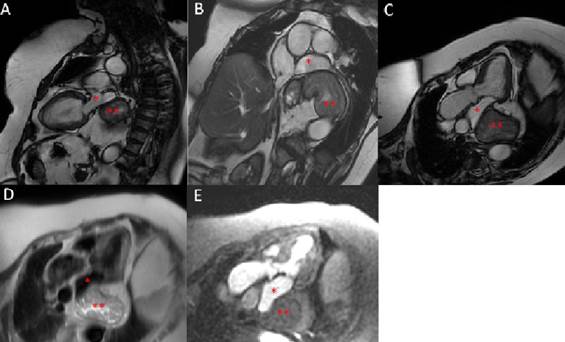

Paciente de sexo femenino de 67 años, con hábito pícnico (peso 90 kg, talla 150 cm) y antecedentes de hipertensión arterial en tratamiento con losartán 50 mg/día. Historia de meses de evolución de disnea de esfuerzo CF II sin causa clara. Historia de dispepsia y episodios de reflujo gastroesofágico. ECG en ritmo sinusal 78 cpm, QRS fino, sin alteraciones de la repolarización. Presentaba ecocardiogramas que eran similares desde hace tres años donde se informa una masa que comprime y/o desplaza la AI sin poder dilucidar con claridad su etiología, asociado a una mala ventana ultrasónica. Por esta razón es enviada por su médico tratante para realización de una RMC con el fin de esclarecer el diagnóstico. La resonancia informa ventrículo izquierdo con volúmenes de fin de diástole y fin de sístole normales, FEVI conservada y destaca la presencia de una masa extracardíaca en el sector posterior de la AI, que desplaza y comprime parcialmente a esta y la vena pulmonar inferior izquierda; por características morfológicas y caracterización tisular corresponde a estómago. En suma, gran hernia hiatal con desplazamiento y compresión parcial de AI y vena pulmonar inferior izquierda (figura 1).

Figura 1: Resonancia magnética cardíaca. A-B-C) Secuencias de cine donde se puede observar una masa extracardíaca en el sector posterior de la aurícula izquierda (*) que corresponde a la cavidad gástrica (**), compatible con hernia hiatal. D) Secuencia ponderada en T2. E) Secuencia de perfusión.